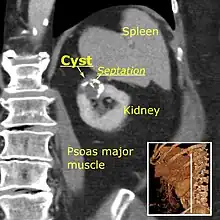

Peripelvic versus parapelvic cysts

Non-contrast CT (at left) showing peripelvic fluid accumulations, which may be hydronephrosis. CT urography (at right) reveals non-dilated calyces and pelvises. The fluid accumulations are thus peripelvic cysts.

Parapelvic cysts originate from around the kidney at the adjacent renal parenchyma, and plunge into the renal sinus. Peripelvic cysts are contained entirely within the renal sinus, possibly related to dilated lymphatic channels. When viewed on CT in absence of contrast, they can mimic hydronephrosis.[14] If symptomatic, they can be laparoscopically decorticated - removal of the outer layer or cortex.[15]